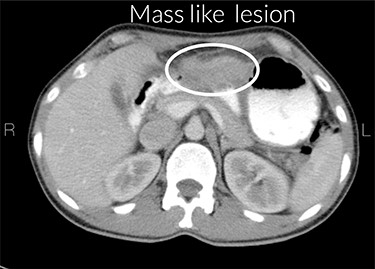

CT scan report

Increased gastric wall thickness was observed with emphasis on antropyloric region and the lesser curvature with maximum thickness of 21 mm accompanied by fat stranding around the same areas. Evidence of partial stenosis with mild dilatation of stomach was seen. Contrast agent has penetrated through the distal region and no leak of contrast agent is observed. Liver, spleen and the pancreas looked normal. No apparent paraaortic lymphadenopathy was observed. No free fluid was observed in the abdomen and the pelvic cavity (Figs 1 and 2).

At laparotomy, severe adhesions of the omentum, falciform ligament, and left hepatic lobe to the stomach antrum were noted, below which a mass like lesion was felt and observed. The stomach was deformed and dilated, with no evidence of seeding or metastasis in the peritoneal cavity. Separation of the stomach and the liver was not feasible. On this patient, distal gastrectomy, resection of Segment II of the liver en bloc with the stomach and Billroth II were performed. Five days after the surgery, the patient was discharged with stable general condition and food tolerance.